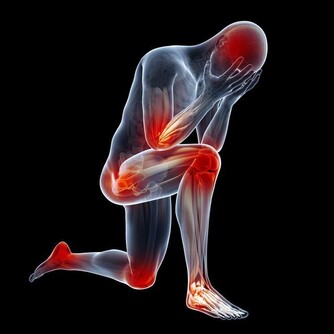

如果放著不管,有些養分和氧氣不能有效到達周邊細胞,就會面臨細胞死亡,而且血液粘稠容易引起血管擁堵,但剛開始發作的時候,並沒有什麼明顯標誌的信號,很容易造成大家的忽視,一般輕者會有頭暈,容易忘東西,腰疼長斑皺紋,失眠,體寒等症狀,嚴重的就會出現動脈硬化,引起心肌梗塞,甚至還會引起腦中風現象。

下肢血管也很重要,但常被大家忽視。多運動能讓更多的毛細血管開放,促進血液微循環;而長期不運動,血管內的垃圾會逐漸累積,形成粥樣硬化斑塊這個「不定時炸彈」,還會影響到毛細血管供血,並且隨時可能被引爆。